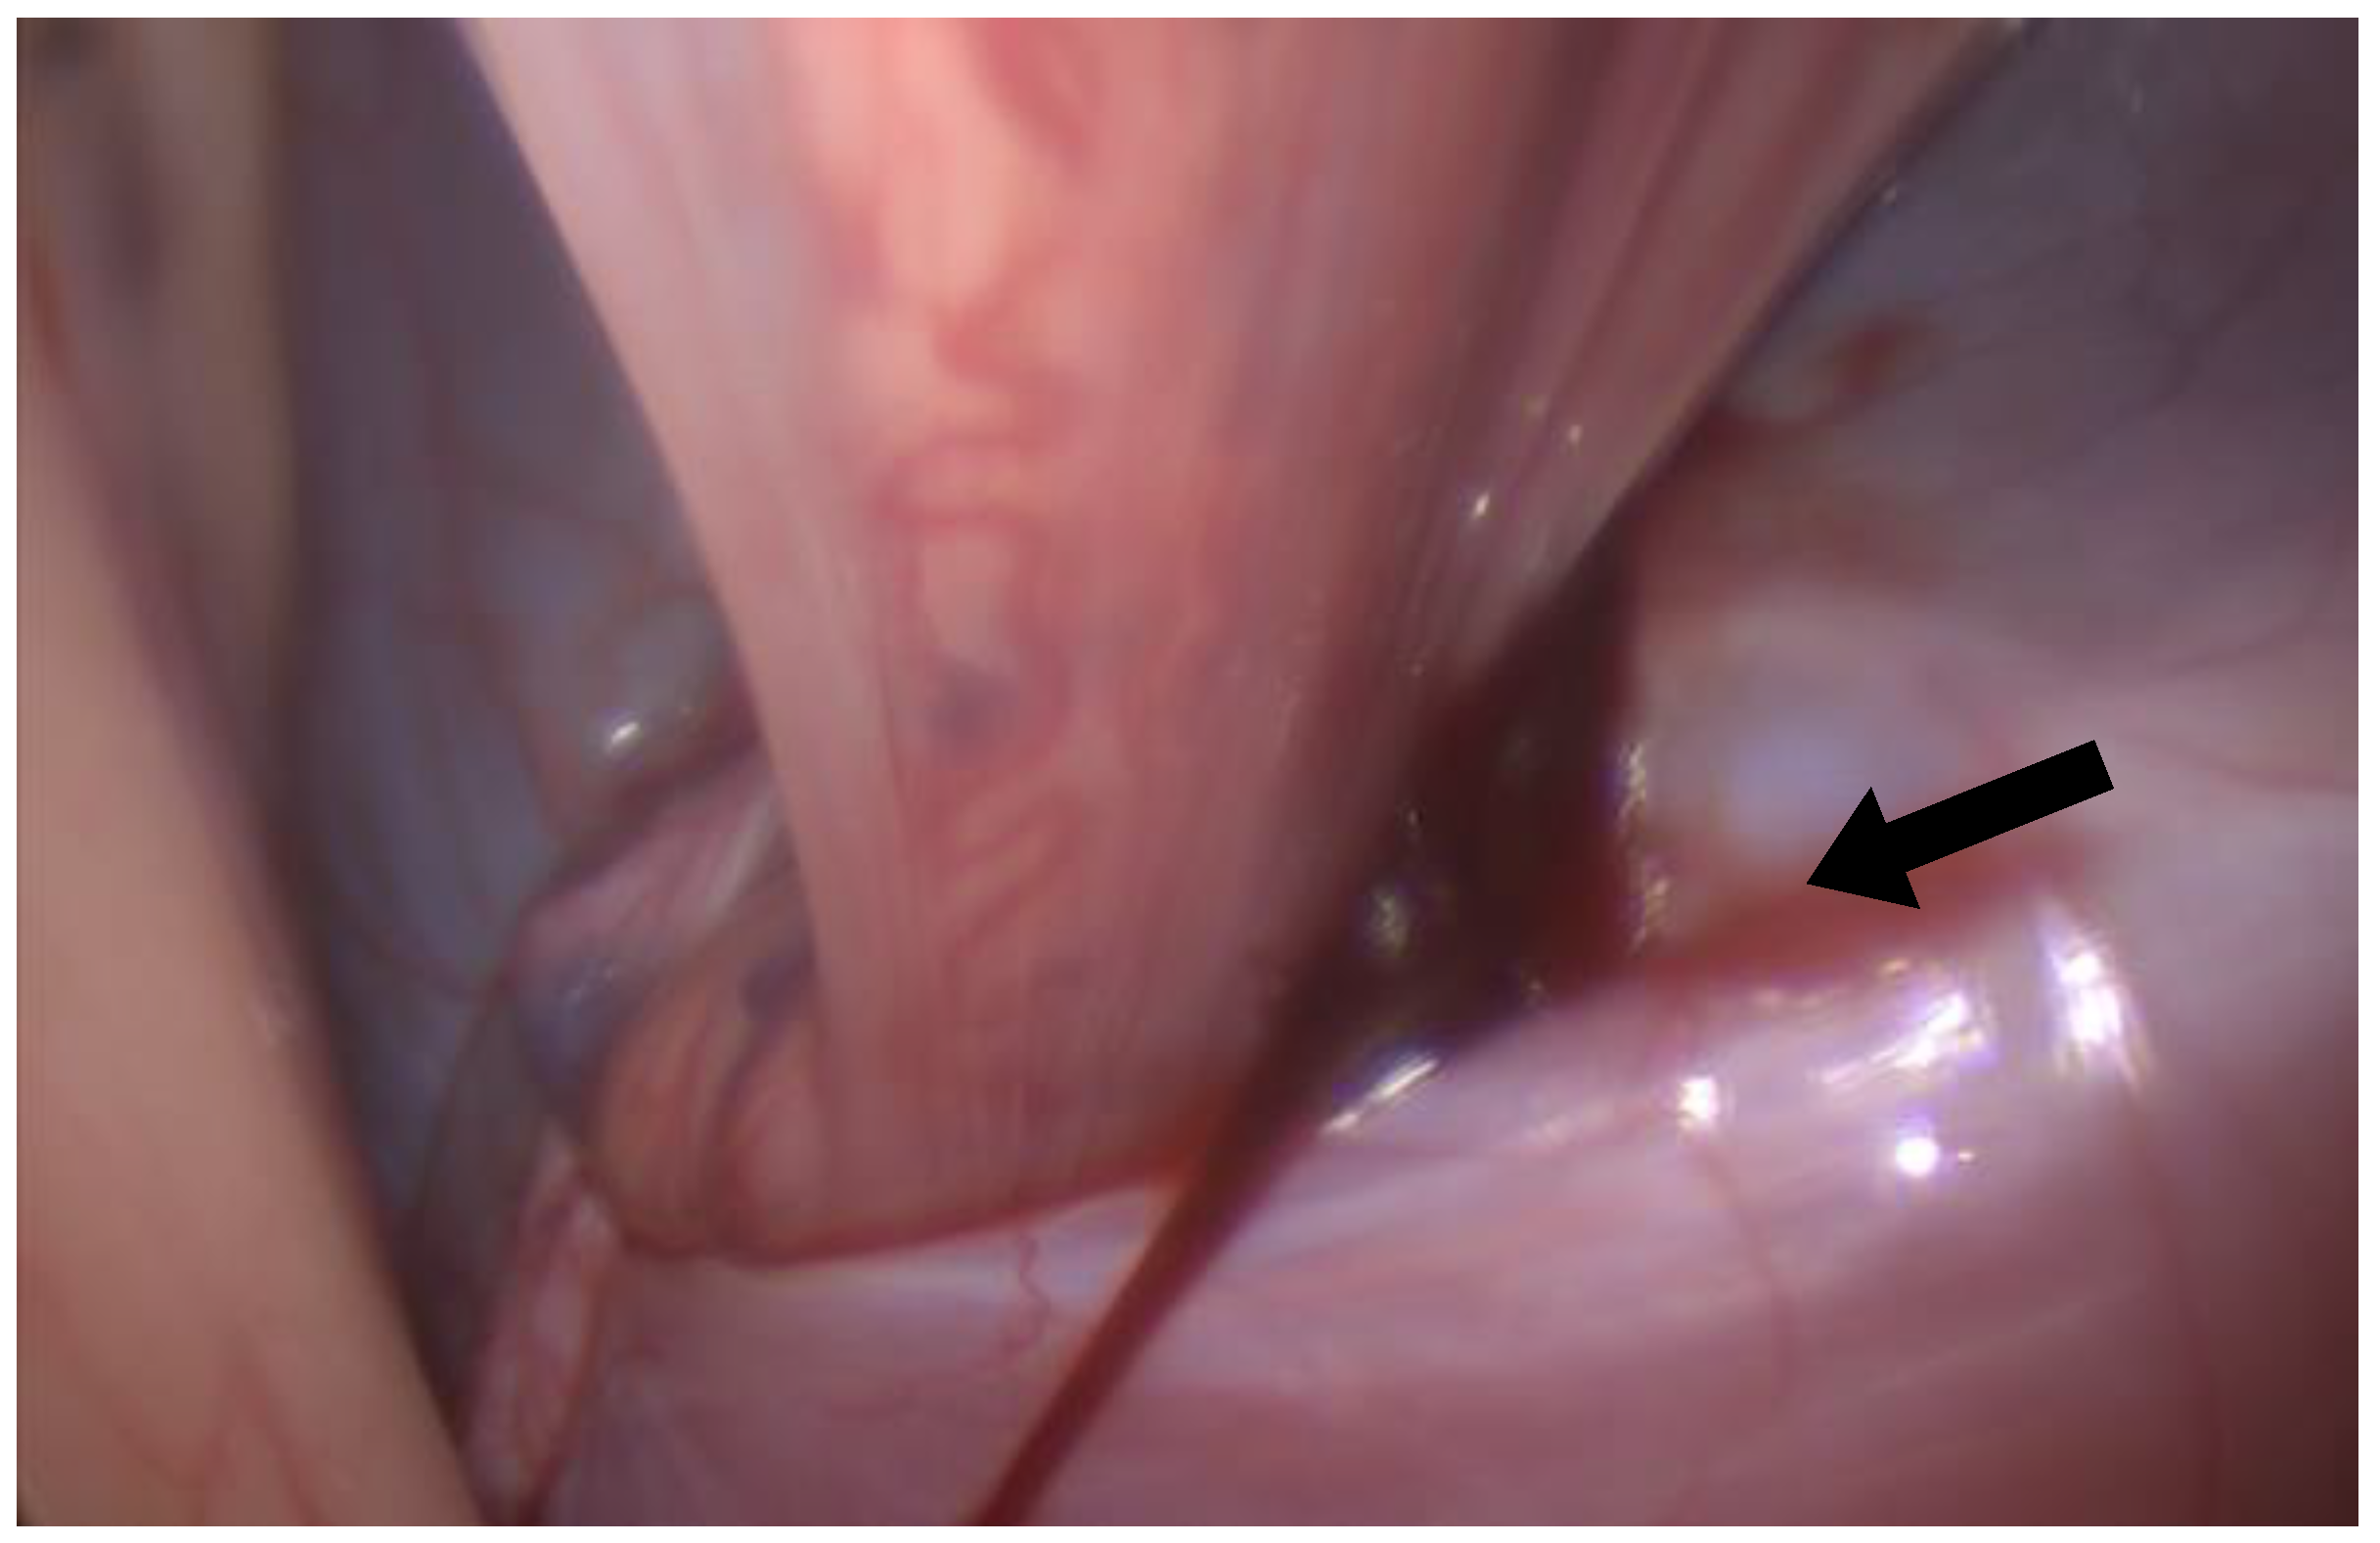

The first portal was positioned standardly in the left paralumbar fossa, dorsal to the internal abdominal oblique crus and halfway between the last rib and tuber coxa (Figure 1). A rigid, 30-degree endoscope was used to confirm cannula placement in the abdomen, and peritoneal insufflation with carbon dioxide to 12 mmHg was achieved (Karl Storz Veterinary Endoscopy, Tuttlingen, Germany). A second port was made about 5 cm ventral to the first for introduction of the bipolar vessel-sealing device (5 mm, 37 cm Covidien Ligasure; Figure 1). The left internal inguinal ring was identified. In both cases, the spermatic cords were visible within the inguinal canal and not retracted into the abdomen; a large clot was visible near the left internal inguinal ring surrounding the spermatic vasculature (Figure 2). In case 1, mild intra-abdominal hemorrhage was also noted. Local anesthetic (5 mL of 2% lidocaine injectable solution, Covetrus, Portland, ME, USA) was administered as a splash block over all spermatic cord components. The testicular artery and other cord components were cauterized using the Ligasure (Figure 3) with the affected sides (left) being double-ligated (Video S1) and having no tissue transection performed. External scrotal hemorrhage stopped immediately after ligation of the affected testicular artery in both horses.

Figure 2. Laparoscopic image of the left internal inguinal ring with a visible clot (black arrow).